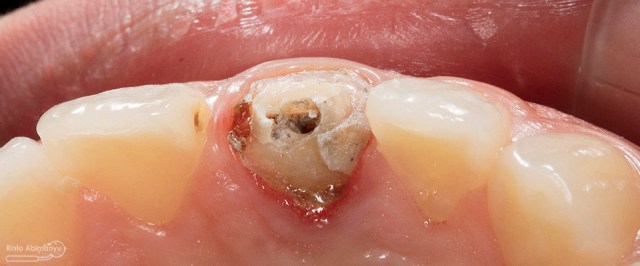

Begini kondisi klinis saat datang…

Foto klinis gigi-gigi anterior yang mengalami fraktur

Dari pemeriksaan radiografis lokasi fraktur menyerempet kamar pulpa pada ketiga gigi tersebut… Saya sampaikan kepada pasien bahwa ketiga gigi tersebut memerlukan perawatan saluran akar terlebih dahulu baru kemudian dilanjutkan dengan restorasi indirek… kenapa saya pilih restorasi indirek? Pertimbangannya adalah sisa struktur mahkota gigi yang ada bila hanya di “sambung” dengan restorasi direk dalam jangka panjang rentan mengalami kerusakan, yang kedua pemilihan warna akan lebih maksimal pada kasus ini…. Pasien setuju dengan rencan perawatan yang saya jelaskan…